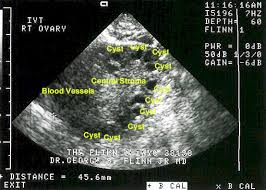

ovary scan

His manner is warm, his smile brisk but well meaning, and today he is excited. The progressive ultrasound scans showed a follicle ripening but the blood progesterone spike of 71 confirms it: Julie has ovulated. Suppressed for five years, this natural act has returned. Mr. Howell oversteps the mark and tells us what he cannot know for sure, that Julie will conceive. ”It’s going to happen now” he announces. This impresario of the ovaries is delighted with his work and I can’t help but be carried along by his sureness and delight. Have you been trying he asks? We have. Julie is one day late and suddenly he is out of the chair ordering her to the bathroom.